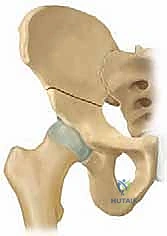

جراحة قطع عظم الحوض الثلاثي (TIO) هي إجراء جراحي يعيد توجيه التجويف الحقي لتحسين تغطية رأس الفخذ وعلاج خلل تنسج الورك، خاصة في الأطفال والمراهقين. يتم من خلال قطع عظام الحوض الثلاثة (الحرقفة، الإسك، العانة) لتمكين دوران التجويف الحقي حول رأس الفخذ، مما يزيد من استقراره ويقلل من خطر التهاب المفاصل المبكر.

من خلال إجراء قطوع دقيقة في عظام الحوض الثلاثة (الحرقفة، الإسك، العانة)، يتم تحرير التجويف الحقي بالكامل ليتم تدويره حول رأس الفخذ، مما يضمن استقراراً ميكانيكياً حيوياً للمفصل، ويمنع الخلع المتكرر، ويقي المريض من خطر الإصابة بالفصال العظمي (التهاب المفاصل التنكسي) المبكر الذي قد يستدعي زراعة مفصل صناعي في سن مبكرة.

4. إعادة التوجيه والتدوير (Rotation & Redirection)

باستخدام أدوات خاصة، يقوم الدكتور هطيف بتدوير التجويف الحقي الحر في ثلاثة أبعاد (للأمام، وللخارج، وللأسفل) حتى يغطي رأس عظم الفخذ بشكل مثالي وميكانيكي سليم. يتم التحقق من الزاوية الجديدة فوراً داخل غرفة العمليات باستخدام جهاز الأشعة السينية المتحرك (C-arm).

5. التثبيت القوي (Fixation)

بمجرد الوصول إلى الوضع المثالي، يتم تثبيت العظام في مكانها الجديد باستخدام براغي معدنية قوية من التيتانيوم أو دبابيس (K-wires). هذا التثبيت يضمن التحام العظام بشكل صحيح خلال فترة التعافي.